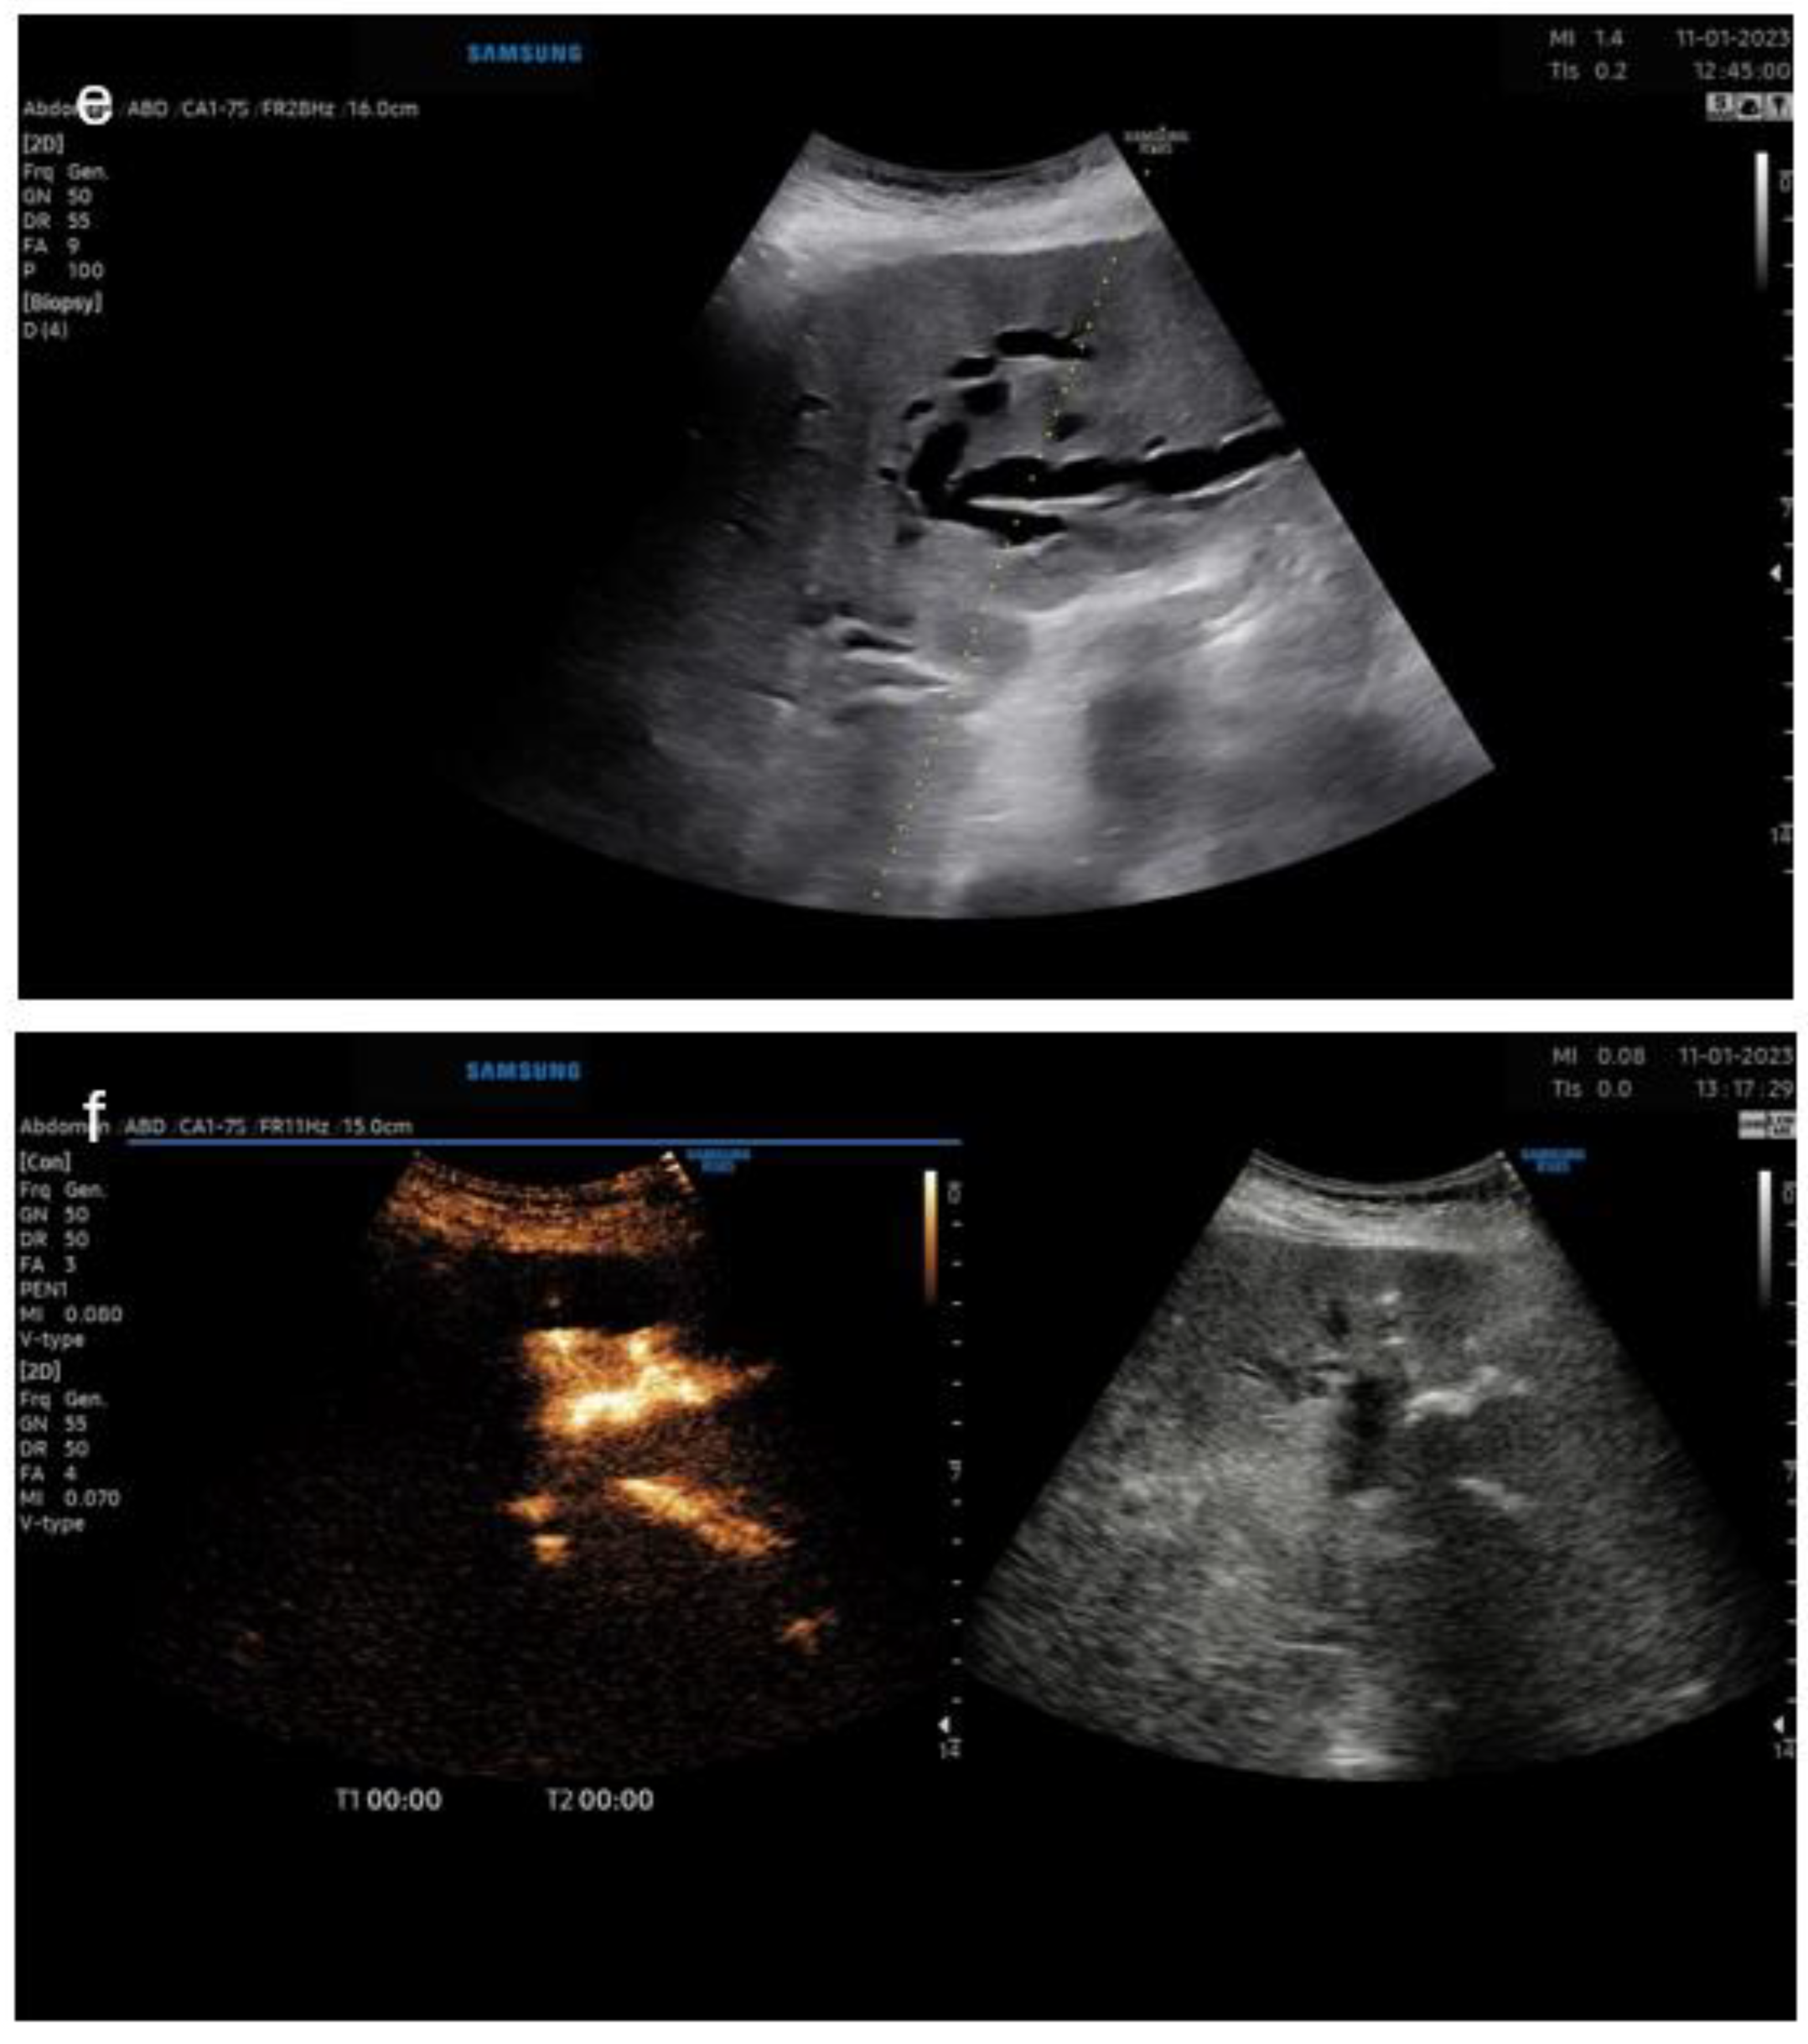

3.5. Pictorial Examples